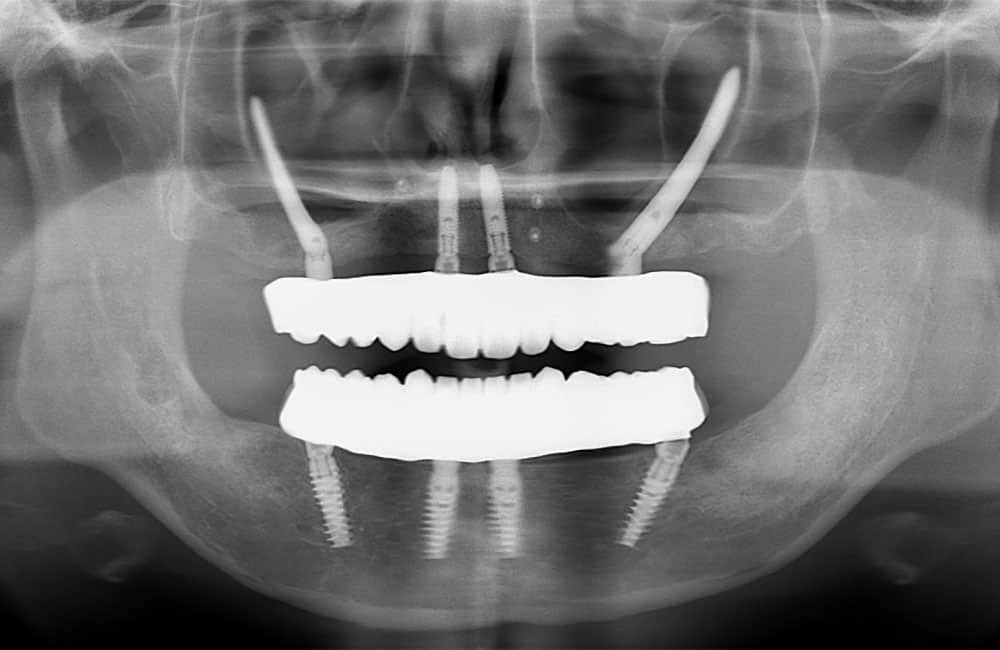

03All-on-4 Double Zygoma

前方、後方にザイゴマインプラントを用い上部構造を支える方法を、一般的にオールオンフォーダブルザイゴマやクアッドザイゴマと呼びます。上顎骨が大きく萎縮してしまったケースに対し、ザイゴマインプラントのみを用いる非常に難易度が高い治療法です。

症例